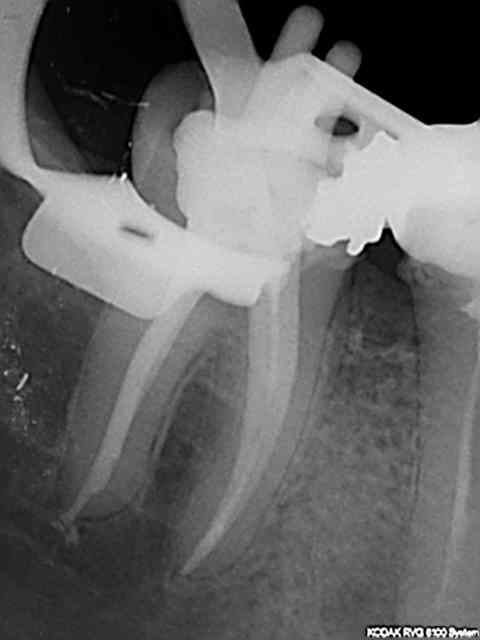

Pas de blouse, pas de radio pour vérifier la longueur.

> Pas de blouse, pas de radio pour vérifier la longueur.

90 mn 2 molar endo + extrac 38. Un peu lent du à la difficulté à anesthésier (30 mn). les crochets apicaux traités comme si ils n'existaient pas avec le r25.

les 6 canaux avec le même r25. Attention toutefois je m'y suis repris à plusieurs reprises pour envoyer le s1 à l'apex (alternance r25 s1) et une bonne ouverture des entrées au largo ainsi qu'une très large cavité d'accès. Je n'ai à ce jour jamais cassé de r25, mais jamais essayé avec les plots en plastique .)

cela n'était pas des petites racines lt 24-25 mm. Big up à la digue qui m'a apporté un très gros confort de travail et m'a fait gagner du temps. Il n'y a que les imbéciles qui ne changent pas d'avis.

Maintenant pour peaufiner l'action du sx avant le passage du s1 un petit coup de r25 pour progresser d'avantage n'est pas interdit (pas de fausse route avec pour l'instant)c'est ce que j'ai fait sur ces 2 molaires ou la radio préop laissait présager un peu de sport. )))

connais pas. Mais une de plus 30 mn, résultat reproductible à un train de sénateur, po pom, po pom.) Radio cone en place facultative mais bon des fois je coupe le bout du cone..